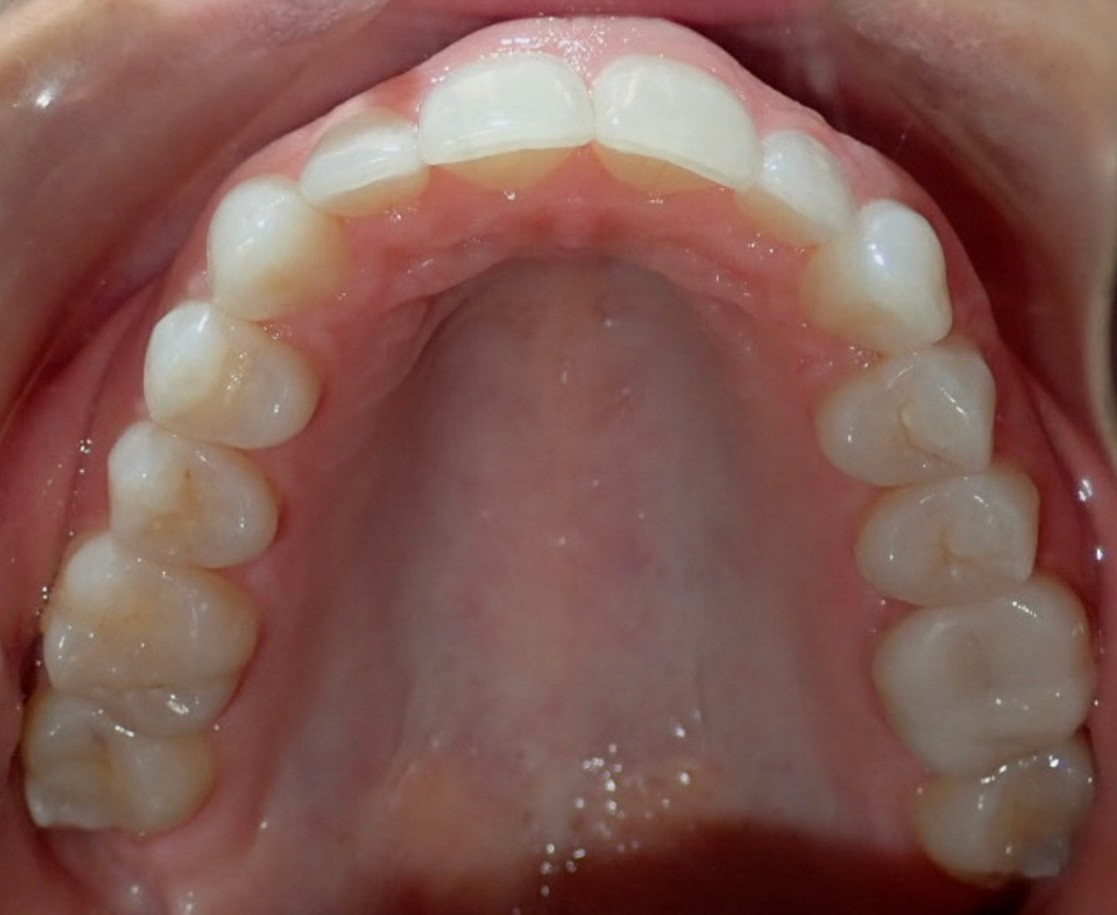

Initial treatment

INTRAORAL